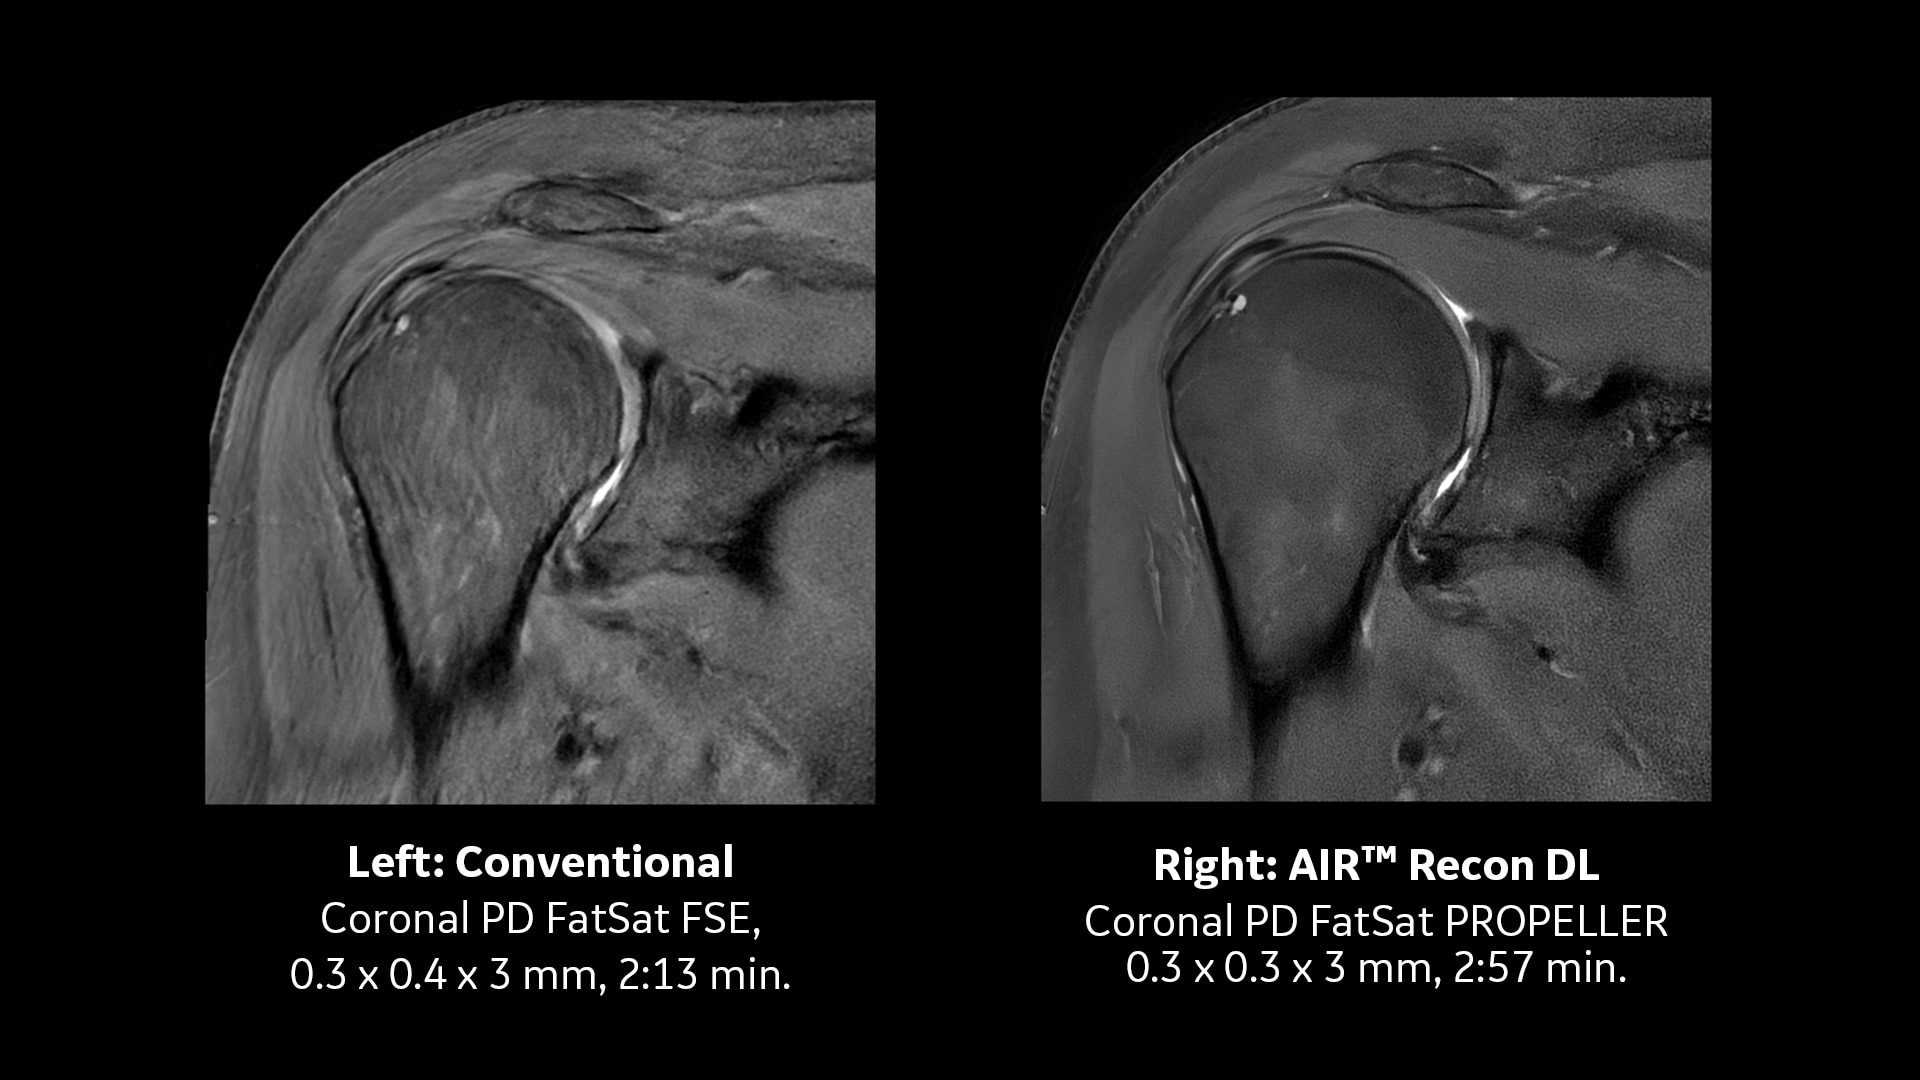

AIR™ Recon DL jetzt auch für 3D und bewegungsunempfindlichen PROPELLER

Unerwartete Patientenbewegungen stellen bei der MRT immer eine Herausforderung dar, da sie zu Geisterartefakten führen, die die Diagnose behindern können. PROPELLER ist eine radiale FSE-ähnliche Erfassungstechnik, die von vornherein bewegungsunempfindlich ist und die gleichen Kontraste und Gewichtungen wie 2D FSE und DWI aufweist. Mit der MR 30 Version ist AIR™ Recon DL jetzt mit PROPELLER kompatibel, womit die durch Bewegung und Verzerrung erschwerte Anatomiediagnose erleichtert wird.